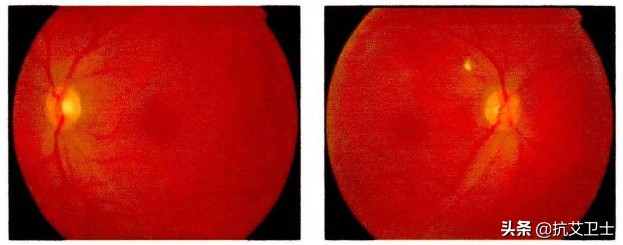

HIV视网膜病变——HIVR

HIVR为非感染性的HIV眼部并发症,发生率高,绝大多数感染者都有发生。HIVR对视力影响较小,起病隐匿,但是随着时间推移,可能引起感染者色觉分辨能力异常、视觉对比度下降、夜视及感光能力减弱[4]。HIVR的严重程度与CD4计数相关,一般基线CD4计数较低者,相关症状越严重。部分学者认为,HIVR是HIV攻击视网膜血管内皮细胞引起的[6]。

HIV相关眼部黄斑病变

HIVR多数情况下并不会对生活有明显影响,但是对于设计、美术从业者来说,HIV感染引起的HIVR无疑会对作品的质量产生干扰、也可能造成夜间驾驶安全性降低。